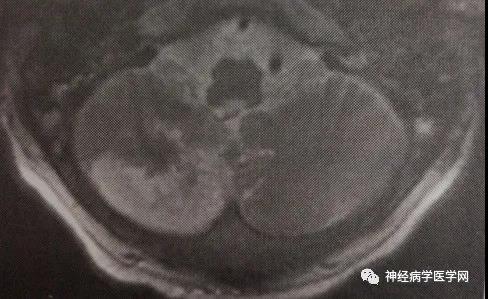

小脑卒中:MRI提示右侧小脑后下动脉小脑分支的选择性梗死,延髓侧部未受损